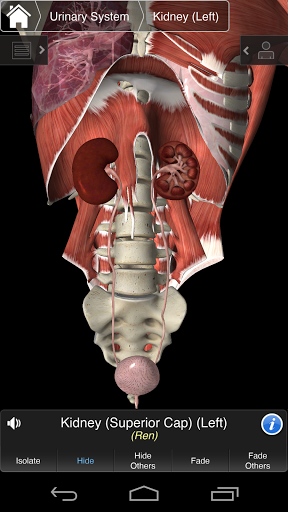

⁃ Урядовий

Основна Анатомія 3 чутлива, візуально приголомшлива і легка. Додаток повністю 3D, що означає, що ви можете переглядати будь-яку анатомічну структуру окремо, а також з будь-якого кута.

---- Більше 4000 дуже детальних анатомічних структур

---- Режим вибору декількох - Сховати / Зменшити / Виділити окремі або кілька структур

---- Правильна аудіо вимова для кожної структури

---- Латинська номенклатура для кожної анатомічної структури